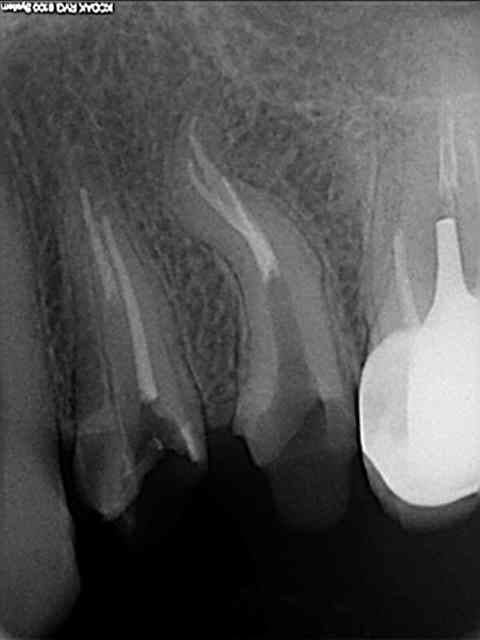

Je commence avec ce bout de F2 que j'ai ostéointégré :( à l'extrémité de la racine Distovestibulaire de cette 17. A l'origine, un "buggage" du localisateur d'apex. Je ferai dorénévement tout de meme une petite rvg de controle....